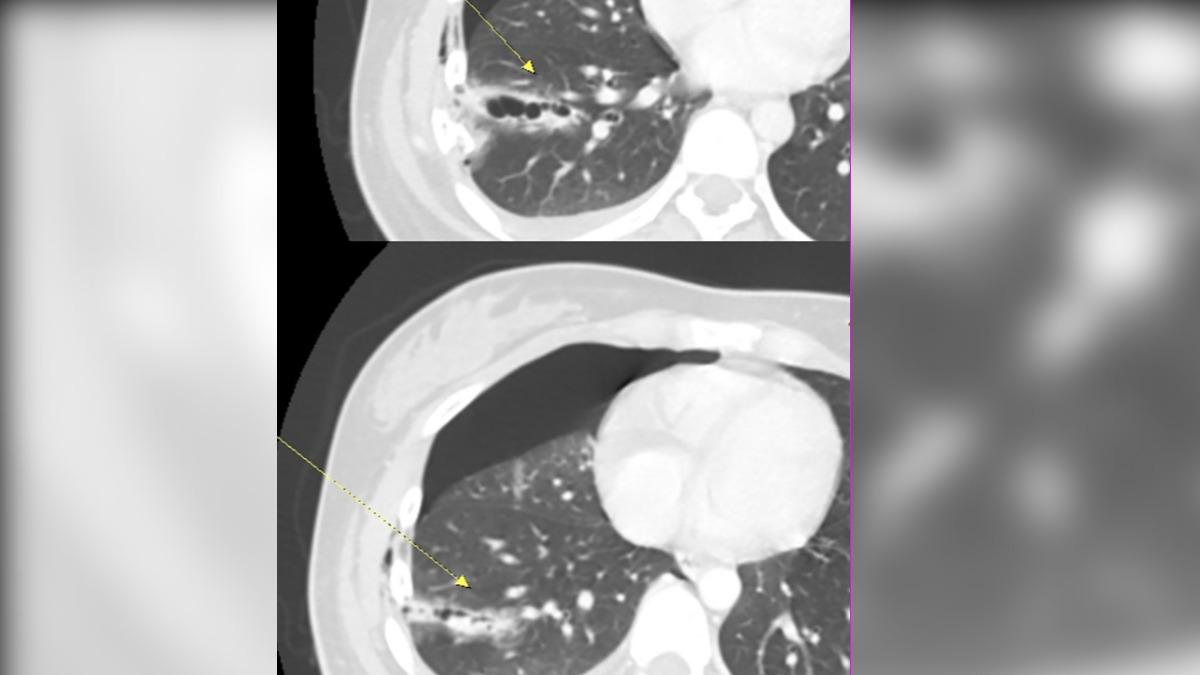

據了解,林女因為騎車與汽車碰撞,被送往急診治療,起初她僅表示右胸疼痛、呼吸稍微不順,原本以為是一般的胸部挫傷,但急診評估發現林女右側呼吸音異常且觸診疼痛明顯,保險起見下安排床邊創傷超音波。結果影像顯示,林女右側胸腔已出現中量積液,進一步進行電腦斷層掃描,確認林女右側第5至7肋骨骨折,其中兩節肋骨明顯插入肺組織,造成肺臟破裂,且胸腔內積血正持續增加,嚴重壓迫肺部擴張。

對此,杜承哲表示,如果只是單純引流,恐無法止住出血,且不能解決肋骨不穩定的劇痛,若不緊急處理,隨時可能因呼吸衰竭或休克而危及生命,最終採用精準內固定手術,以內視鏡微創手術進入胸腔確定骨折處和出血點,清除積血並修補肺臟;再進行肋骨骨折復位固定手術,針對斷裂的肋骨使用專用骨板進行固定。